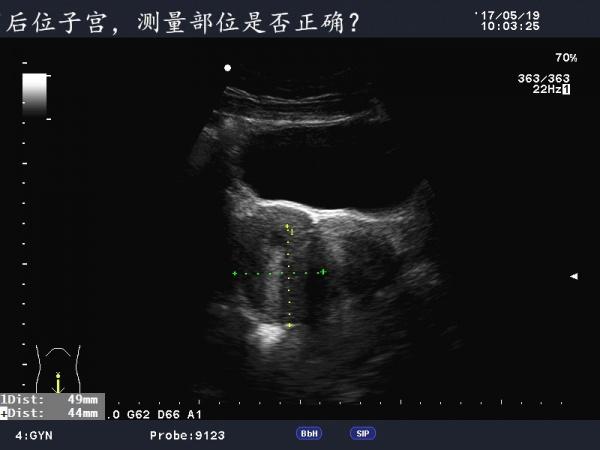

患者女,40Y,因下腹部疼痛就诊,最近一次月经来潮量少且疼痛厉害,以往基本上正常。

于月经第11天行B超检查。